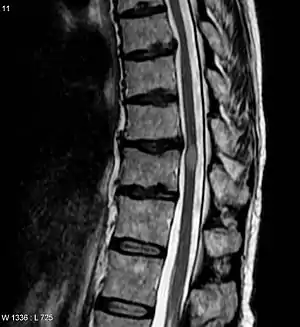

A Mielite Transversa é uma doença neurológica causada por um processo inflamatório das substâncias cinzenta e branca da medula espinhal, e que pode causar desmielinização axonal. O nome é derivado do grego myelós referindo-se à "espinha dorsal", e o sufixo ite, que indica inflamação.

Há uma grande variedade na apresentação de sintomas, que são baseados na parte da medula espinhal que foi afetada e na gravidade dos danos na mielina e nos neurônios na medula espinhal. Os sintomas da MT incluem: fraqueza muscular, paralisia, parestesia ou sensações desconfortáveis nos nervos, dor neuropática, espasticidade, fatiga, depressão, e disfunção sexual, intestinal, e vesical. A MT pode ser aguda ou também pode se desenvolver lentamente. Além disso, existem várias variações no diagnóstico da MT.